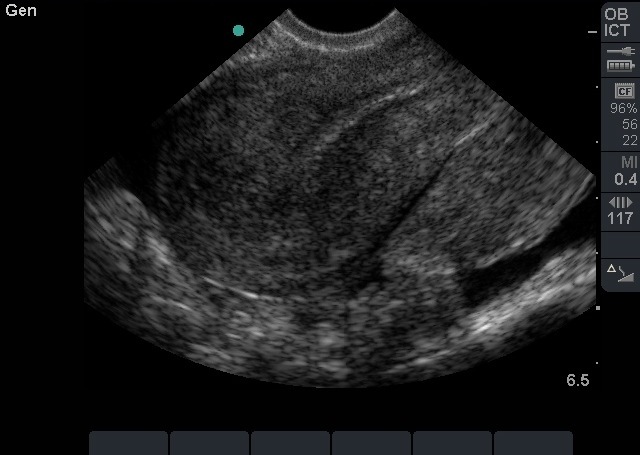

Bild 2: Transvaginaler (TV) Ultraschall des Beckens, ektopische Schwangerschaft, sagittal, leerer Uterus mit freier Flüssigkeit